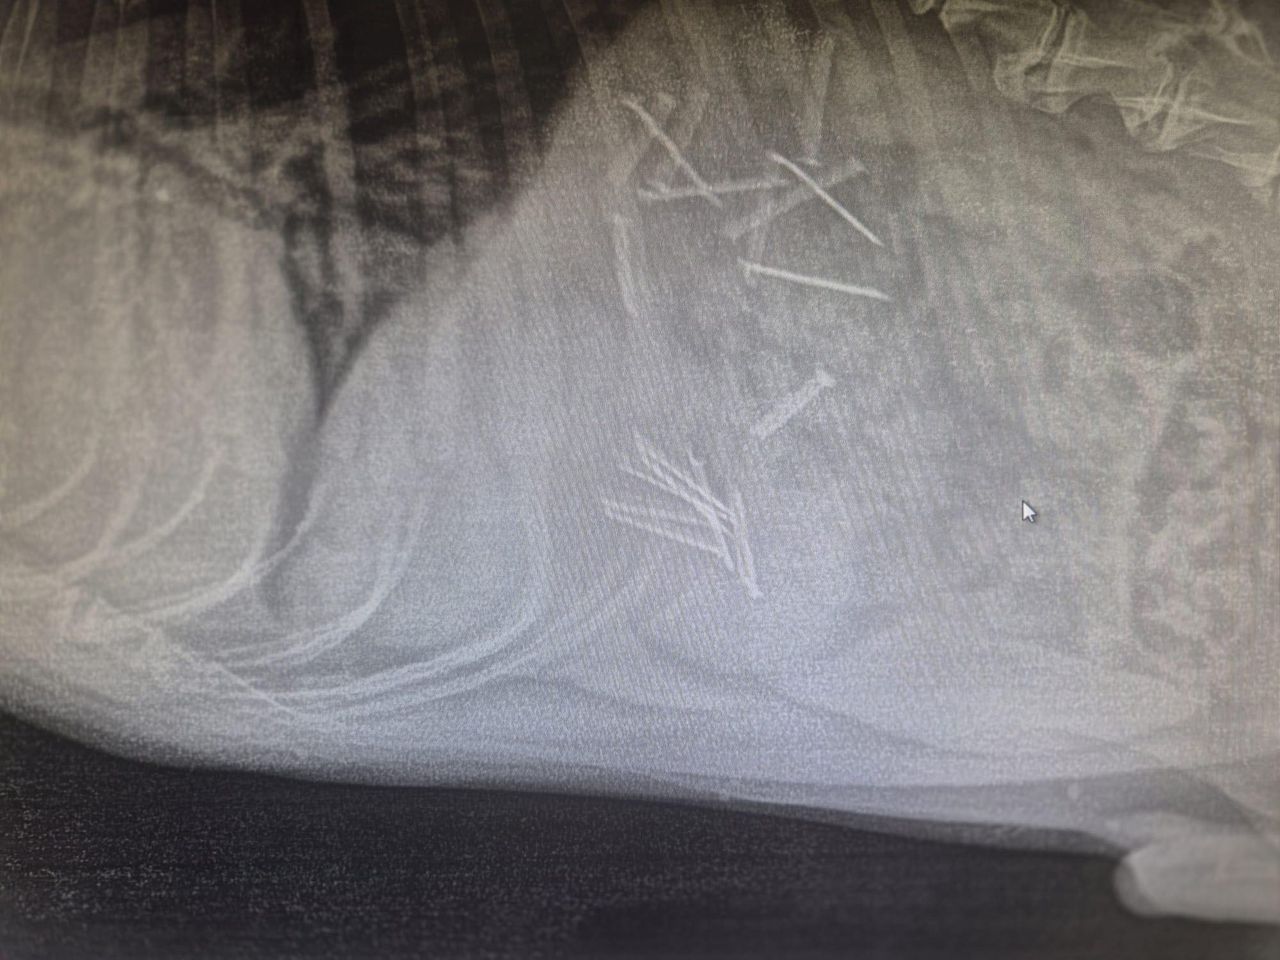

Wypadek w miejscowości Zarębin.Wypadek w miejscowości Zarębin.

Źródło zdjęć: © KPP w Płońsku